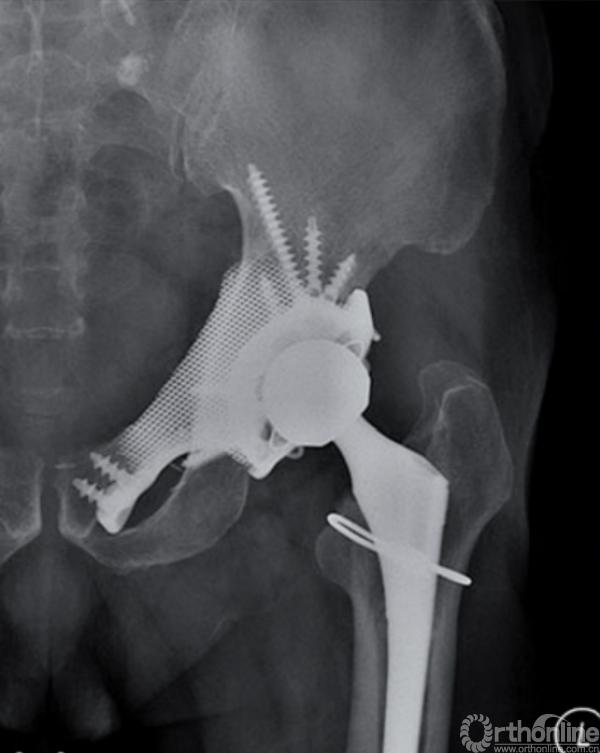

自1971年第一例定制化半骨盆假体投入临床应用起,其设计理念及方法一直在快速发展[16]。随着3D打印技术的应用以及假体设计进一步改良,定制化半骨盆假体的预后已经得到了长足进步[17-26](图4)。

图4 3D打印定制化半骨盆假体